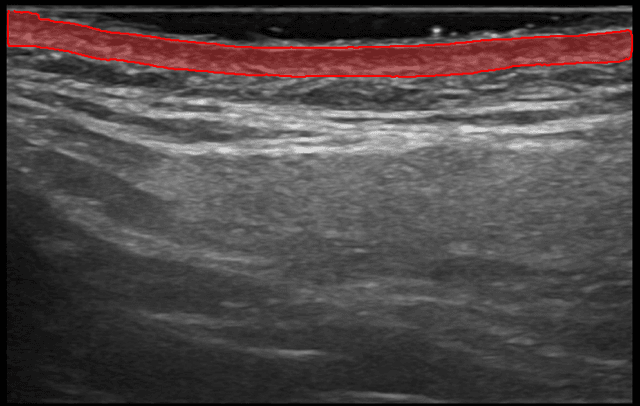

Nuestra IA segmenta instantáneamente tu capa dérmica. Obtén mediciones precisas de el grosor y el área de la dermis.